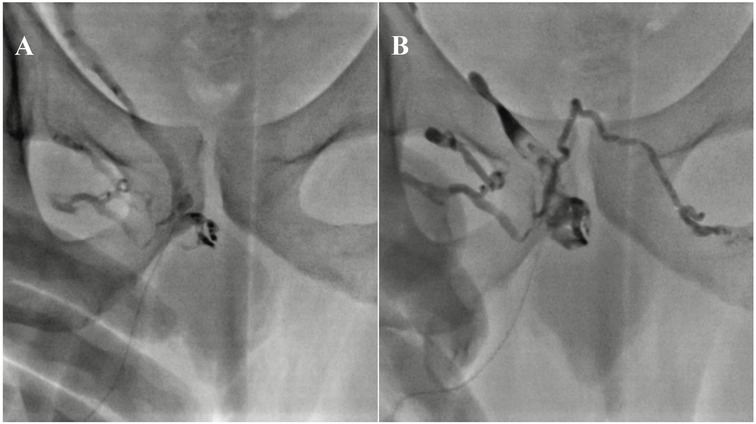

A Narrative Review of Endovascular Treatment in Addressing Arterial and Venous Erectile Dysfunction

Erectile dysfunction (ED) is a worldwide health concern and clinical condition for men, leading to high medical costs and imposing significant emotional and psychological burdens on sufferers annually. ED is associated with multiple causes, including psychological factors and organic issues such as arterial insufficiency and venous leakage. Endovascular treatments have emerged as promising options for managing ED, offering minimally invasive procedures that can improve blood flow to the penis and restore erectile function. Different endovascular interventional approaches have been implemented with varying success rates and therapeutic impacts, and efforts continue to optimize these methods (both arterial and venous) for maximum effectiveness and minimal invasiveness. This narrative review aims to provide an overview of endovascular treatments for arterial and venous types of ED, discussing their mechanisms of action, efficacy, safety, and future directions.